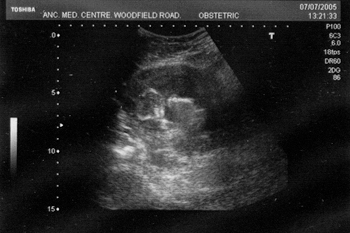

Isabel seems to have put on a bit of weight recently...Hey, I guess the secret's out anyway. We are bothTHRILLED to pieces. Below is a picture of junior at 12 weeks. Actually I thought of a Ridley Scott Film when I first saw this picture and voiced this concern to the midwife. I won't be doing that again. Not to be recommended. The Picture is older than this entry, in fact, junior is now 15 weeks and expanding…

The young un-developed...